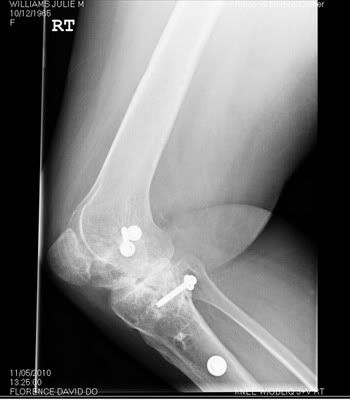

Most people don't understand why I am the way I am. I hope these x-rays give them a better idea of what I have to deal with every single day.

My right knee: